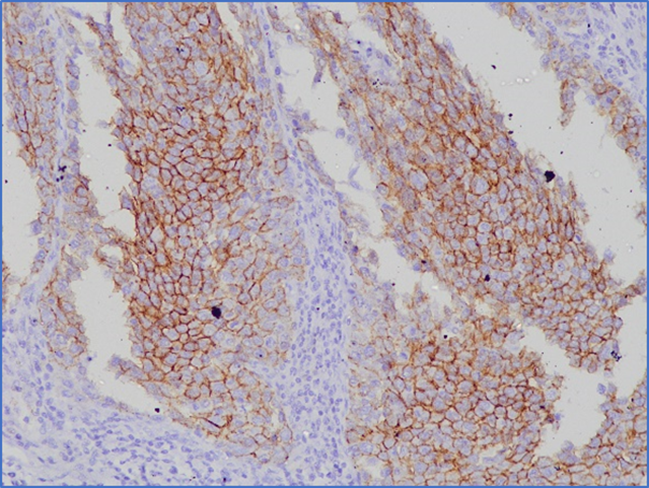

Expressions of Ki-67 and E-cadherin are given in FIGURE 1 and FIGURE 2, respectively. Of the 25 NSCLC tissue samples, 15 exhibited positive expression for E-cadherin, while 15 were negative for Ki-67 expression. Of the 15 NSCLC tissues with positive E-cadherin expression, Ki-67 was positive in 6 cases. Conversely, among the 10 NSCLC tissues negative for E-cadherin, Ki-67 was positive in 4 cases. However, no statistically significant association (P=0.99) was identified between Ki-67 and E-cadherin expression (TABLE 1). No statistically significant association was found in the expressions of both Ki-67 and E-cadherin with age, sex, family history of lung cancer, histological type, tumor differentiation, and lymph node metastasis except E-cadherin expression and co-morbidity of the patients (P=0.01).

FIGURE 1 Expression of Ki-67 in non-small cell lung cancer tissue